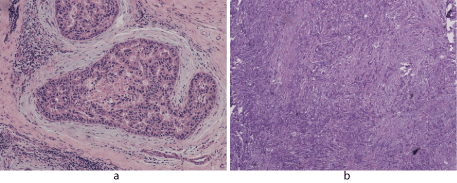

Samples were retrieved from 104 ductal breast cancer patients, tissues were made into paraffin blocks and HE staining, diagnosed by pathological doctors. Pathological type: 9 cases of carcinoma in situ (Fig.1A), 95 cases of invasive ductal carcinoma (Fig.1B).

Figure 1.